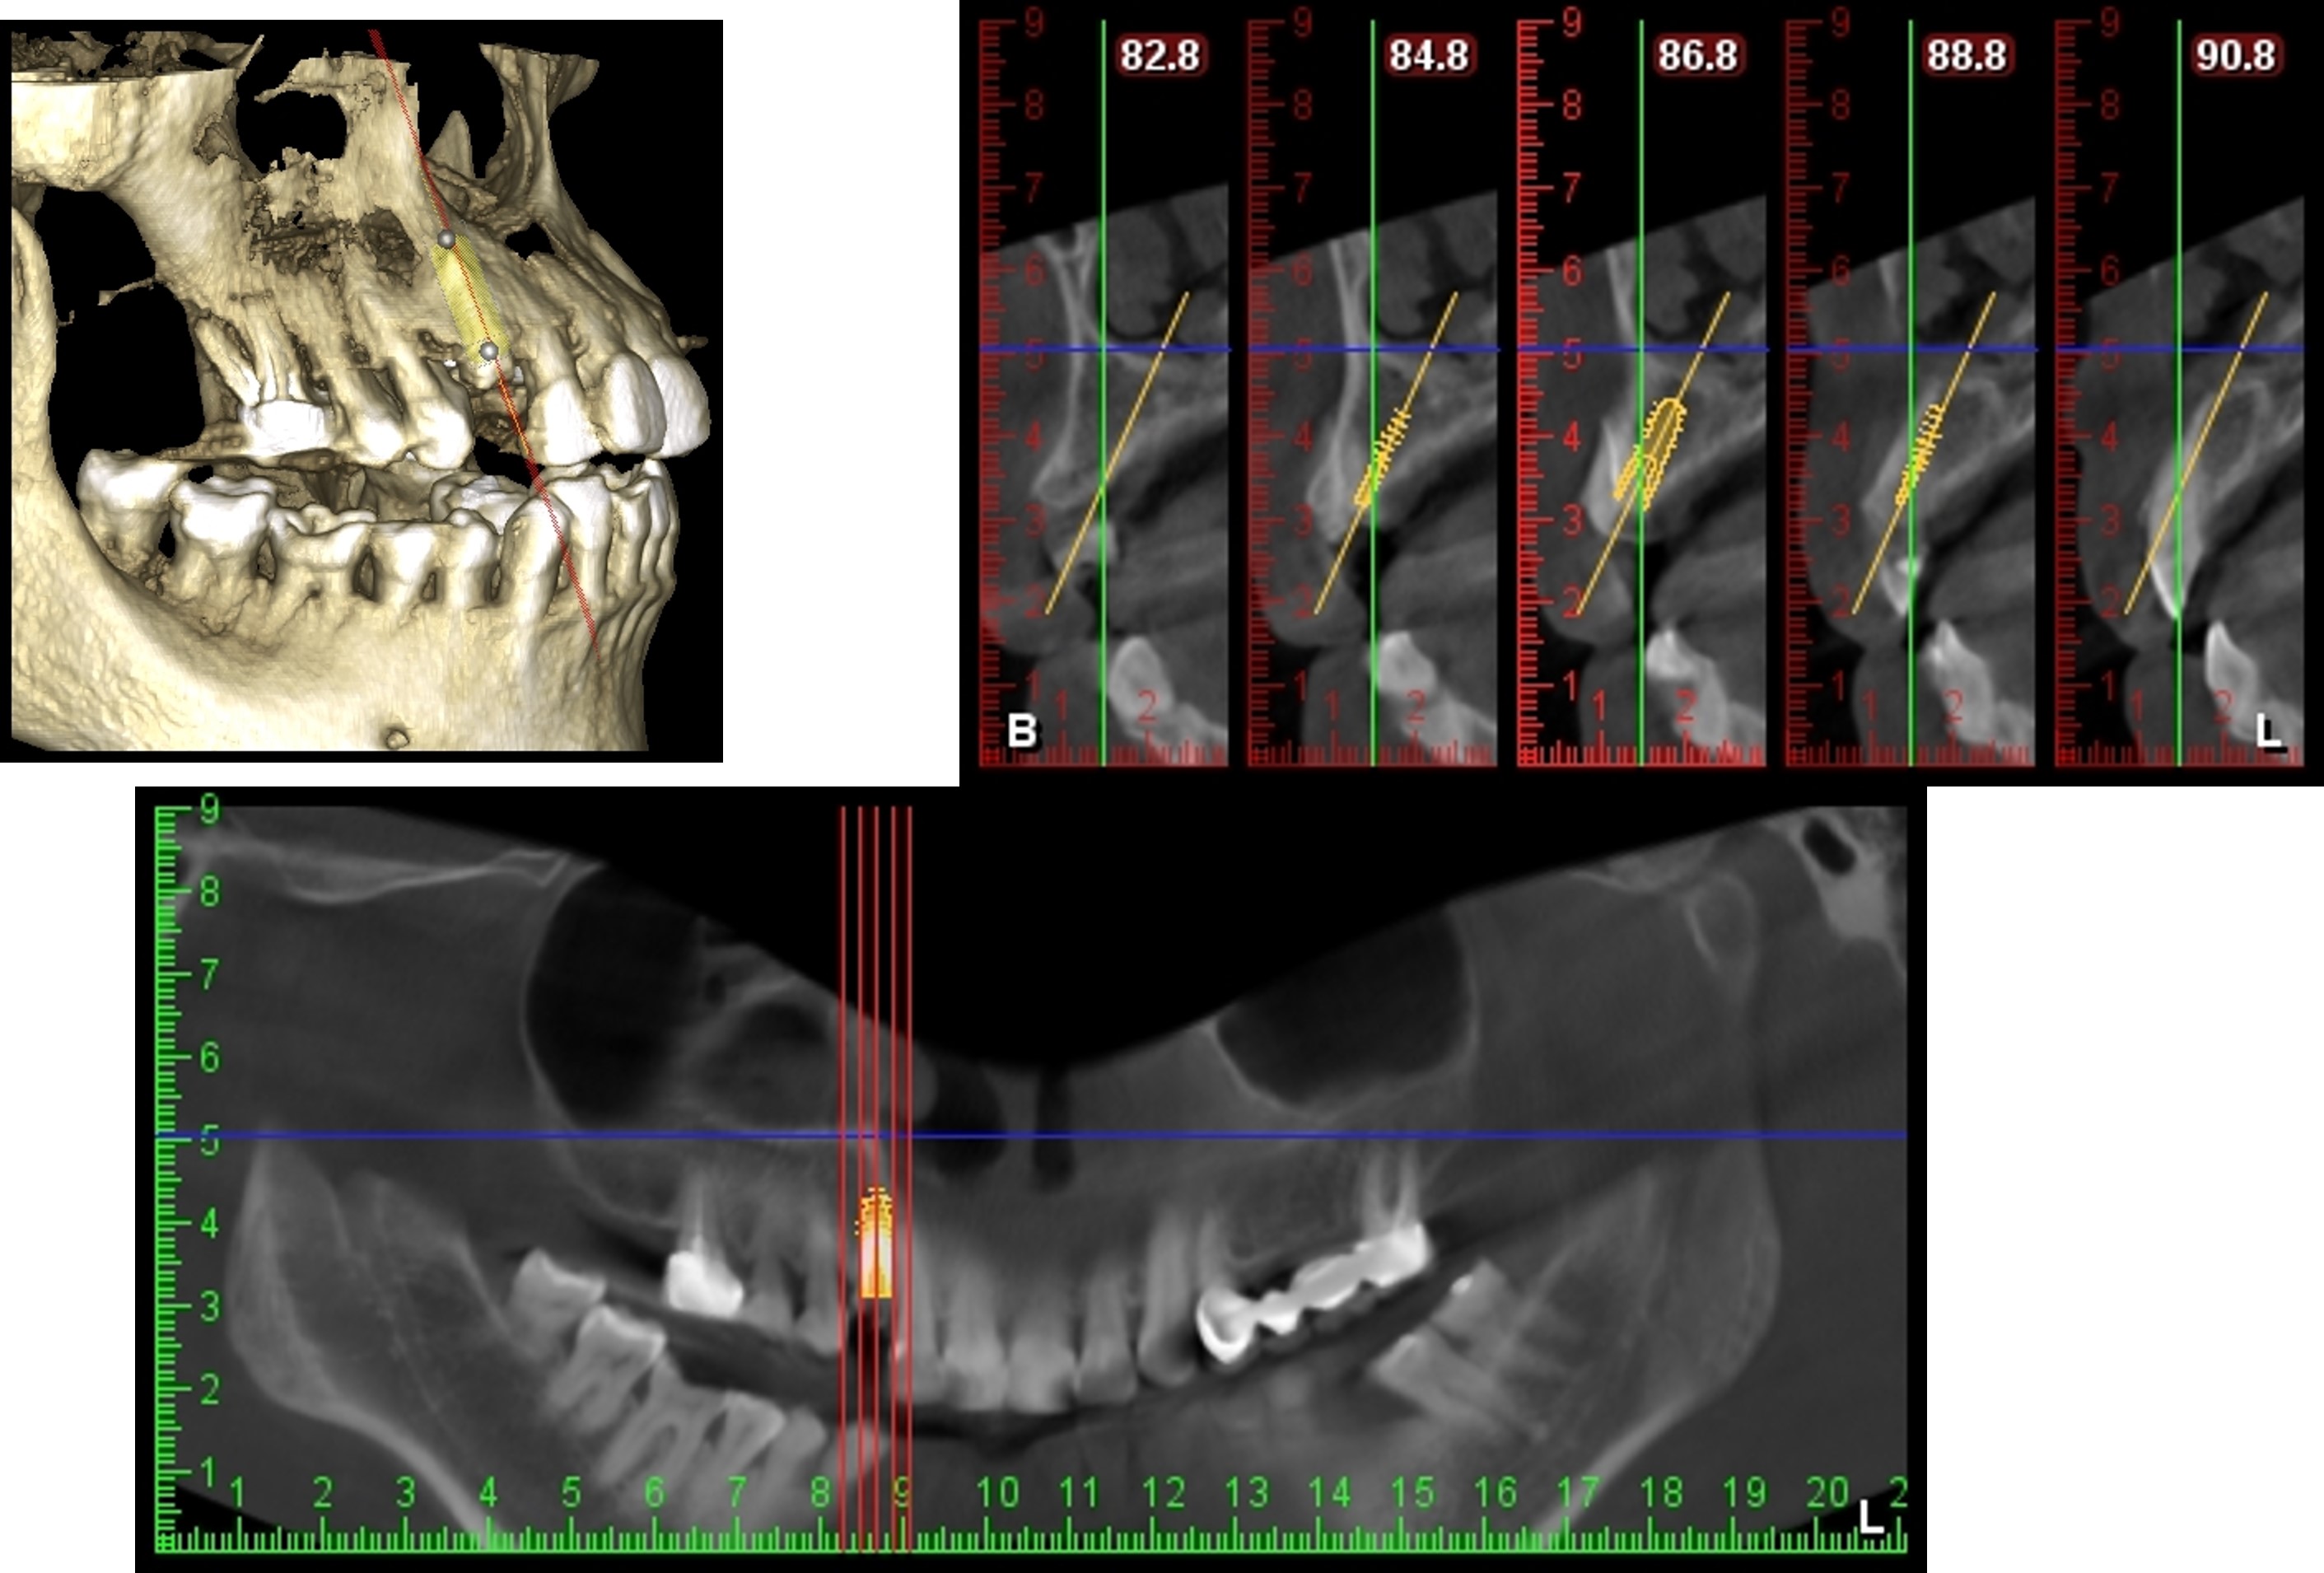

植牙規畫模擬